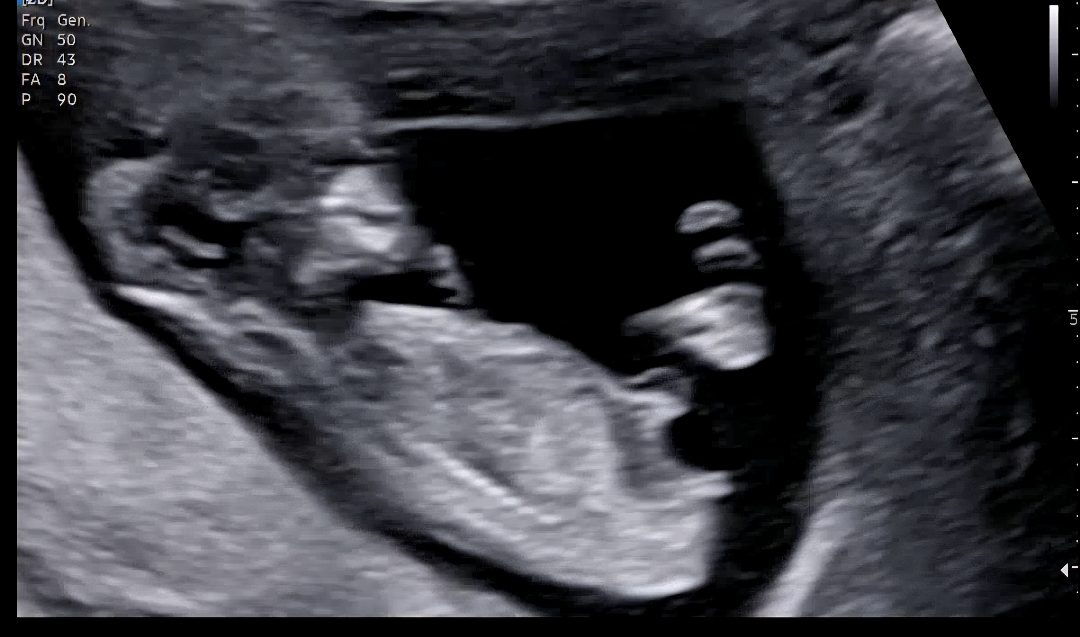

혹시 각도법 도사님계신가요🥹

둘짼데 ㅋㅋㅋㅋㅋ 너무너무 궁금합니당

아들같아요🙂

각도상 아들 같아요!

각도가 아들인거같아요~

아들이요~!